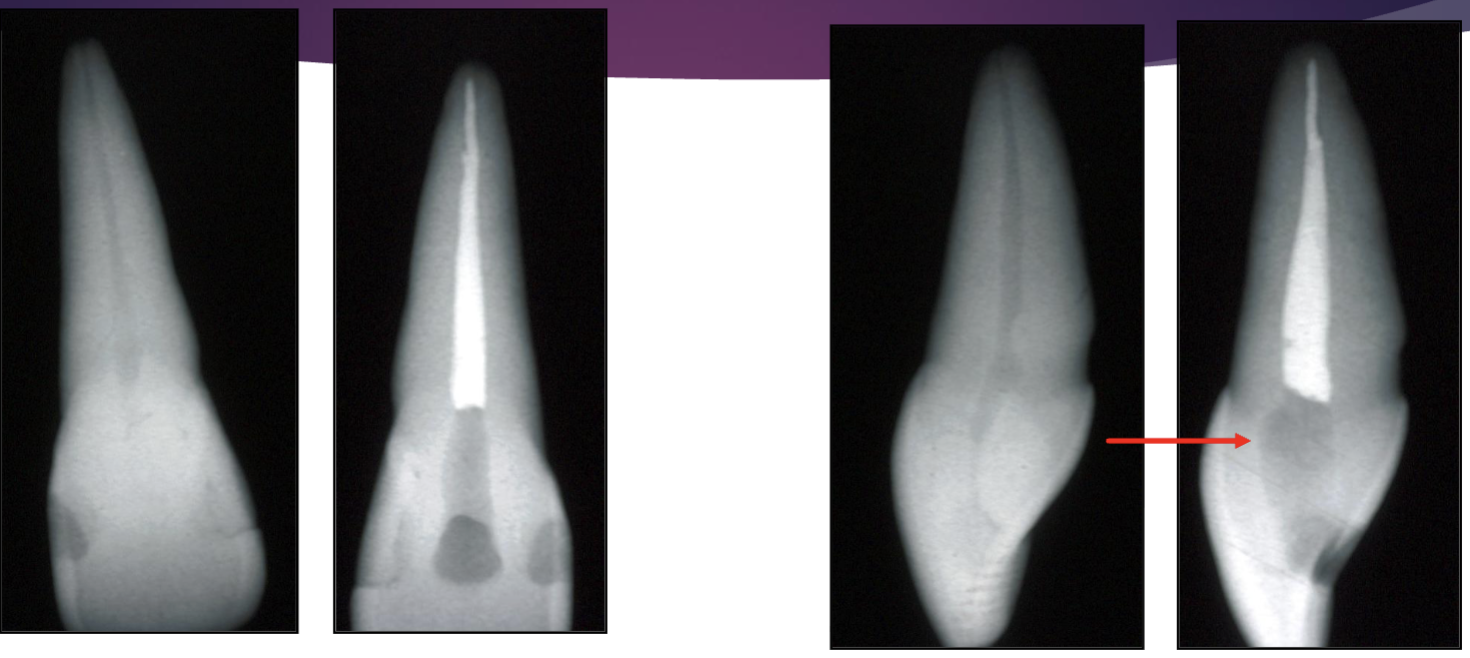

is this an example of straight line access

NO: need to open orifice (where red arrow is pointing) to be able to get straight line access

what does the canal shape look like in the mid root vs the apical third of a maxillary central incisor

both are round

what does the canal shape look like in the mid root vs the apical third of a maxillary lateral incisor

can be round or ovoid

what does the canal shape look like in the mid root vs the apical third of a mandibular canine

usually oval, mid root can start separate and then join in apical third